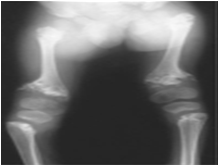

MetaphysealChondro Dysplasia